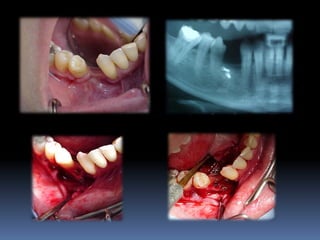

Ausência ou perda dental x implantes

Periodonto íntegro               perdas de suporte

Atrofias ósseas x implantes

Procedimentos reconstrutivos       Compensação protética

prognóstico

favorável                        desfavorável